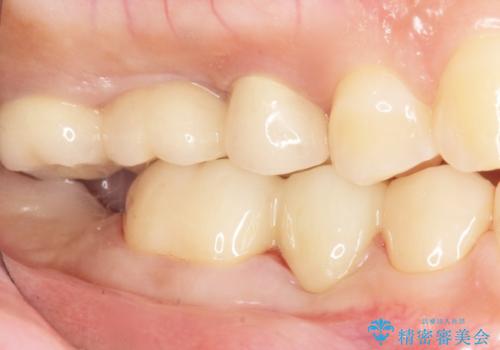

![[ 途中からの治療 ] 他院で行った根管治療後のセラミック治療の症例 治療後](https://seimitsushinbi.jp/wp/wp-content/uploads/2021/08/8f8d20667c9105de80d21401ceb4478d-500x350.jpg?v=1629978239)

![[ 歯牙破折 ] 違和感のある大臼歯 ブリッジ治療の症例 治療後](https://seimitsushinbi.jp/wp/wp-content/uploads/2021/08/2e4ccba27e1ea02fdacf49749694bbb1-500x350.jpg?v=1629711051)